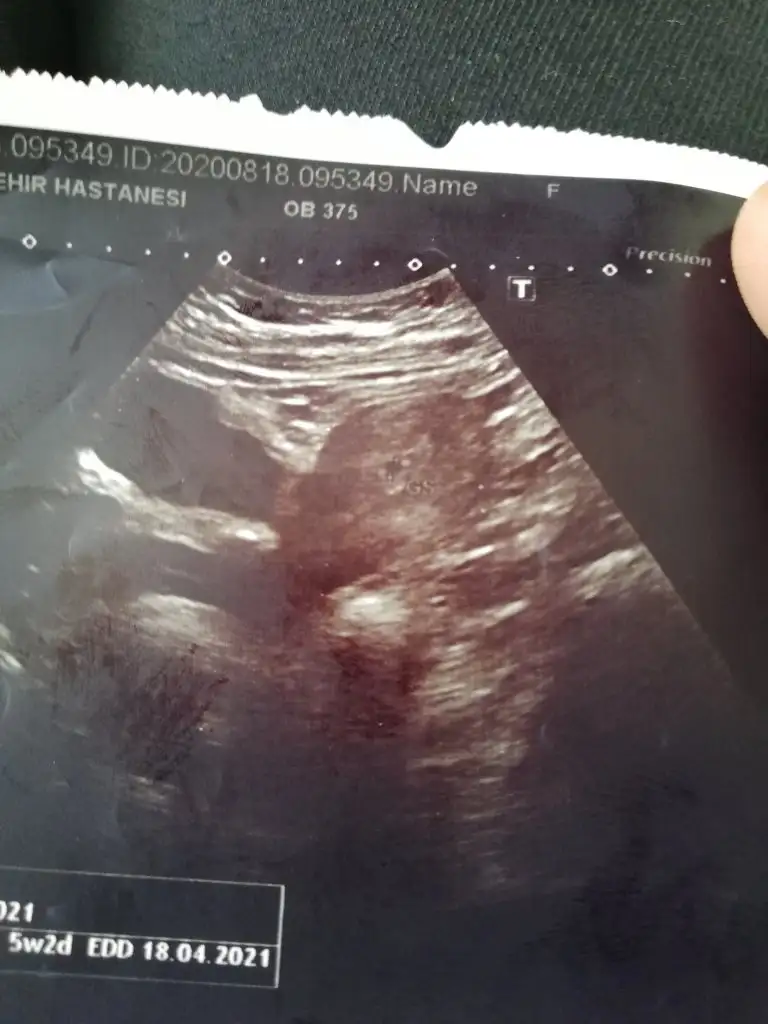

Kızlar ilk ultrason footlarınızı atın bakalım ramzi teorisi mi ne varmış bakalım kimlerinki tutacak. Ben dün gittim sata göre 6+1 ama ultrasona göre 5 +2çıktı.keseyi gördük doktor 2 hafta sonra tekrar gel hem kalp atışını duyup bebği de görebileceğimizi söyledi. Bu da sevgili keseceğimiz. Sağlıklıcakla kucağımıza alacağımız günlere.

• IMG_20200818_172249.webp

IMG_20200818_172249.webp

32,2 KB · Görüntüleme: 59